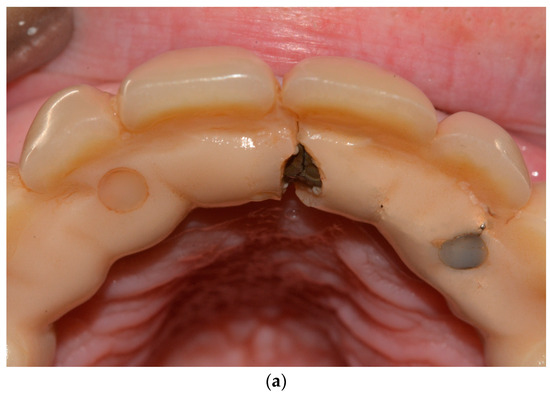

The second step consists of the examination of the soft tissues next to the implants and the prosthesis. In this phase, transmucosal decubitus (Figure 4a), fenestrations, hypertrophy (Figure 4b), fistulas (Figure 4c), and dehiscence (Figure 4d) must be identified and registered. In these cases, the prosthesis is unscrewed to assess peri-implant tissues and the morphology of the prosthodontic framework; investigations are conducted regarding any difficulties in maintaining hygiene due to inadequate space between the gums and the prosthesis. The devices to be used in this phase are retractors (i.e., Optragate, Ivoclar Vivadent, Schaan, Liechtenstein), gauze, and optical magnifiers.

Figure 4.

(a–d) Intraoral pictures of possible biological complications of zygomatic implants: decubitus (a), hypertrophy (b), fistulas (c), and dehiscence (d).